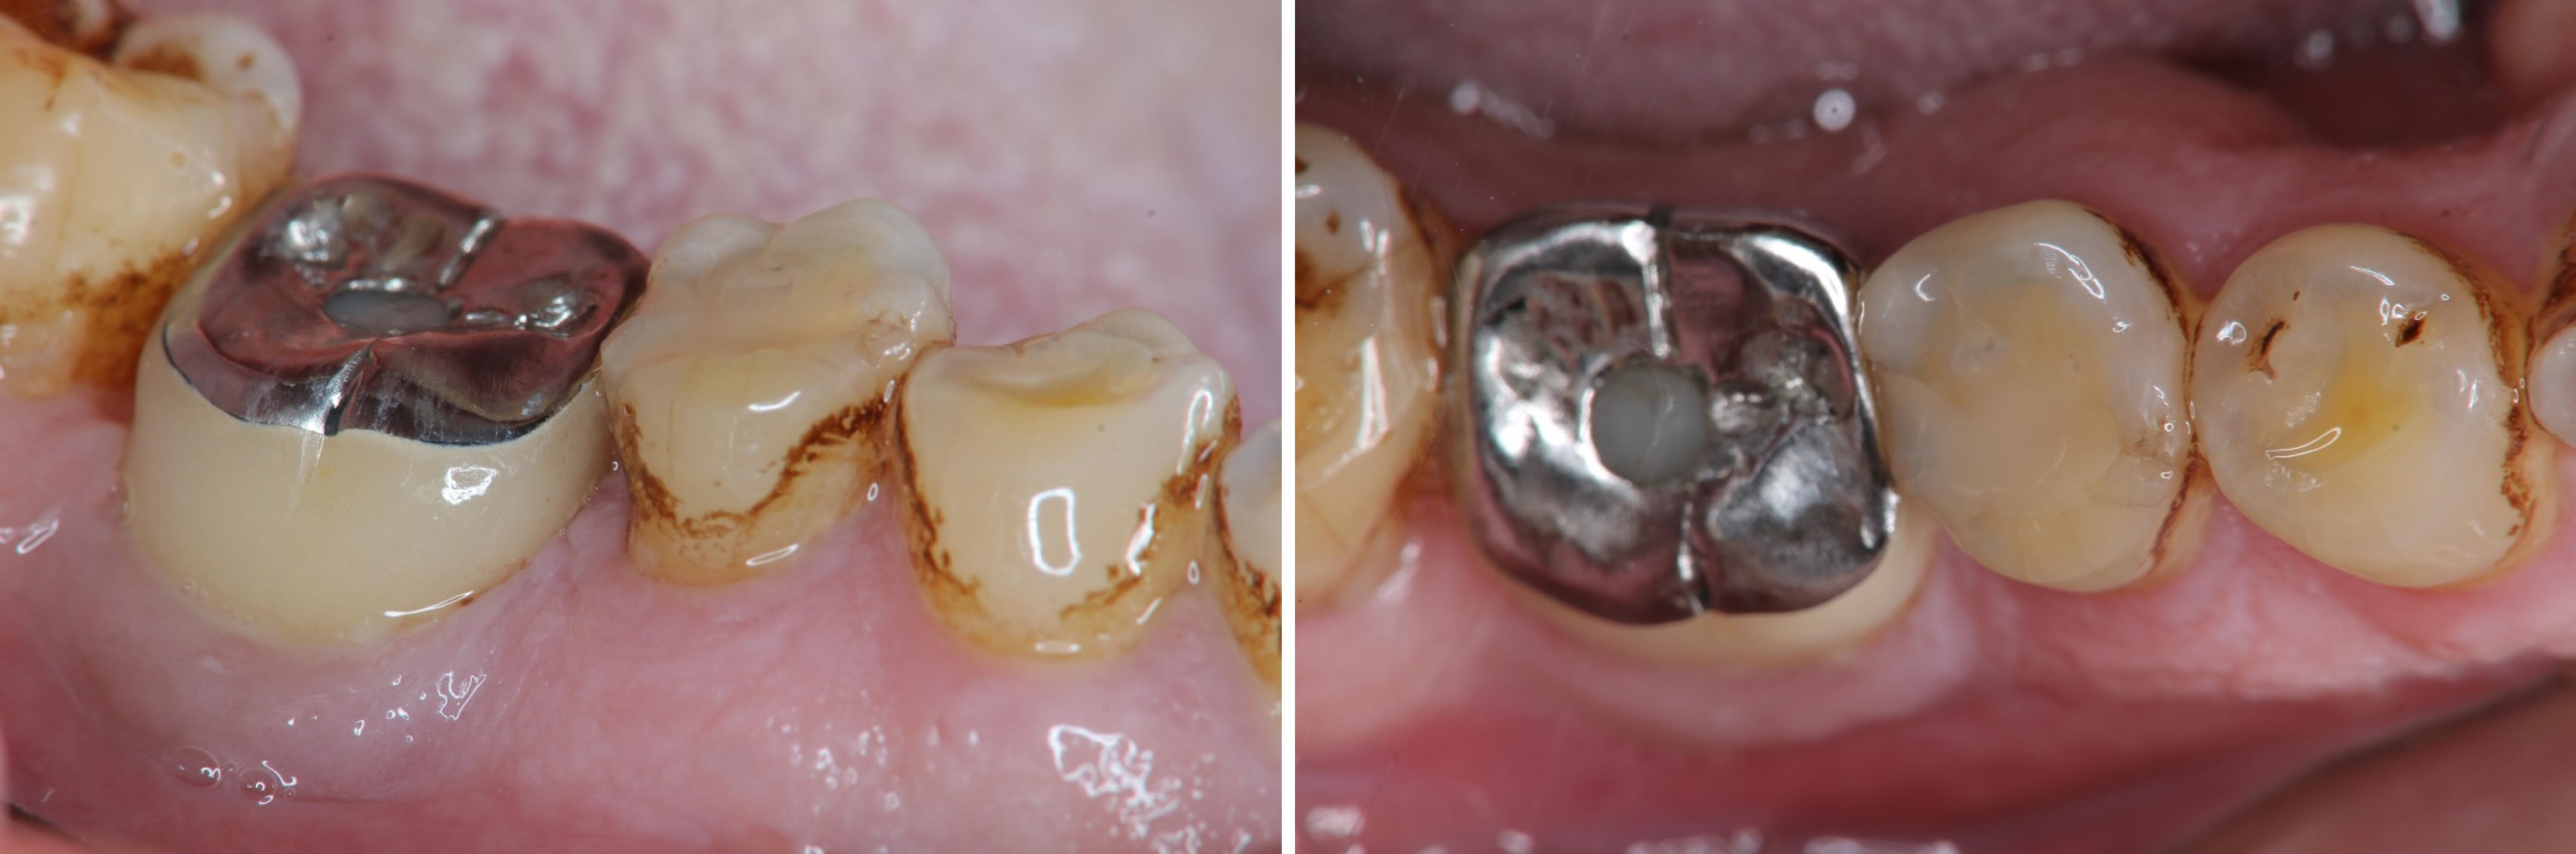

治療後口內照

患者的咀嚼機能逐漸恢復正常

術前、術後比較